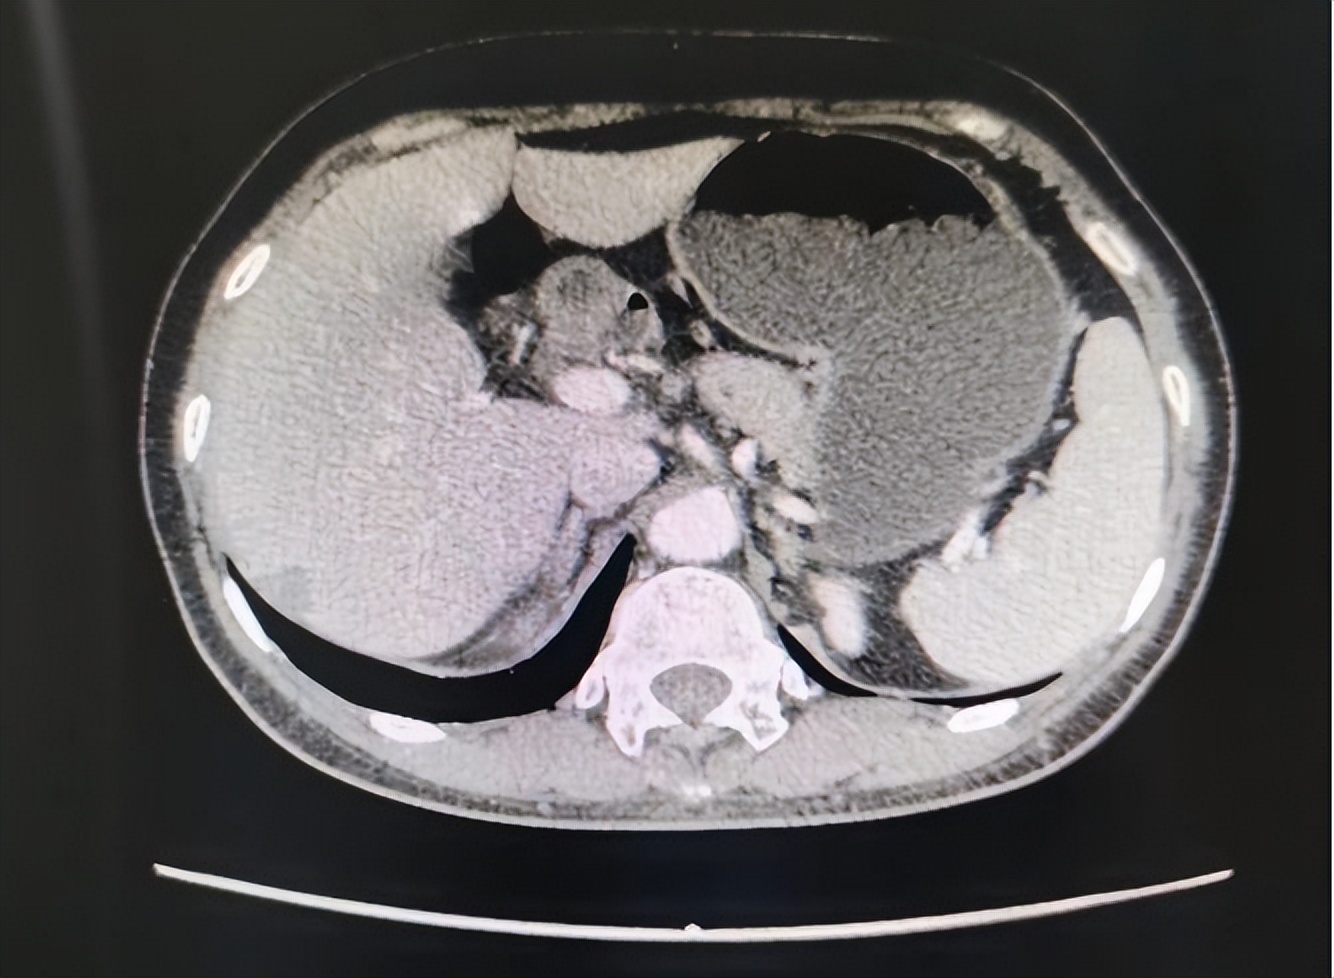

2023-06-12行CT复查:右乳癌术后化疗后复查,与2023-4-5 CT比较:降结肠下段肠壁增厚伴其旁、肠系膜间、腹主动脉下段左旁多发饱满及稍肿大淋巴结,考虑恶性病变侵犯腹膜可能性大,肝右叶结节较前稍增大(2.51*2.02cm),仍考虑转移可能性大。

2023-06-13在我院行PET/CT示:肝脏类圆形低密度灶,FDG代谢增高,病灶体积较前增大;右侧附件区见一结节状FDG代谢增高灶,FDG代谢较前降低,病灶体积较前似见减小,病灶与邻近肠道分界不清,考虑转移可能;腹膜后及降结肠周围多发稍大淋巴结,FDG增高。肿瘤标记物变化趋势: